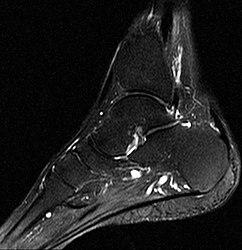

Um ein Knochenmarködem festzustellen, muss eine Magnetresonanztomografie (MRT) durchgeführt werden. Diese Flüssigkeitsansammlung unter der Knochenhaut verursacht starke Schmerzen, die auch ohne Belastung des betroffenen Bereichs anhalten können.